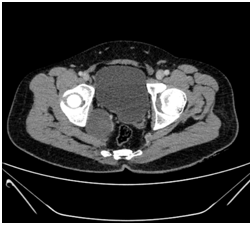

30 years old gentleman arrived with complaints of lower abdominal discomfort for 6 months with vague right iliac pain with normal gut and bladder habits. He experienced no other co-morbidities. Clinical examination findings were normal. Blood investigation was done within normal limits. Ultrasound abdomen showed a complex cyst with internal echoes and absence of vascularity in the right side of the pelvis. Contrast CT abdomen revealed non enhancing unilocular cystic mass on the right lateral pelvic wall.MRI, abdomen with gadolinium revealed T1 hypotenuse, T2/STIR heterointense enhancement within the lesion. Colonoscopy was normal. He underwent laparotomy under general anesthesia, through Pfannenstiel extra peritoneal approach mass lesion of size 8cm x 6 cm identified in the right pelvic region in the course of obturator nerve producing the compression over the lateral wall of the bladder without any infiltration of the bladder and bowel. It was arising from the nerve bundle, the lesion was well capsulated. It was highly vascular with blood supply from the branches of internal iliac arteries. The feeding arterial branch was ligated, outer capsule opened and an inner mass removed completely after leaving the capsule intact in view of nerve injury. Haemostasis achieved, postoperative period was uneventful. Histopathology revealed a mass of size 8x6.5x3.5cm section shows unencapsulated lesion comprised of spindle cells with wavy nuclei prominent myxoid stroma and scant collagen, conclusive of as Neurofibroma (Figures 1-4).

Figure 1 CT abdomen revealed unilocular cystic.